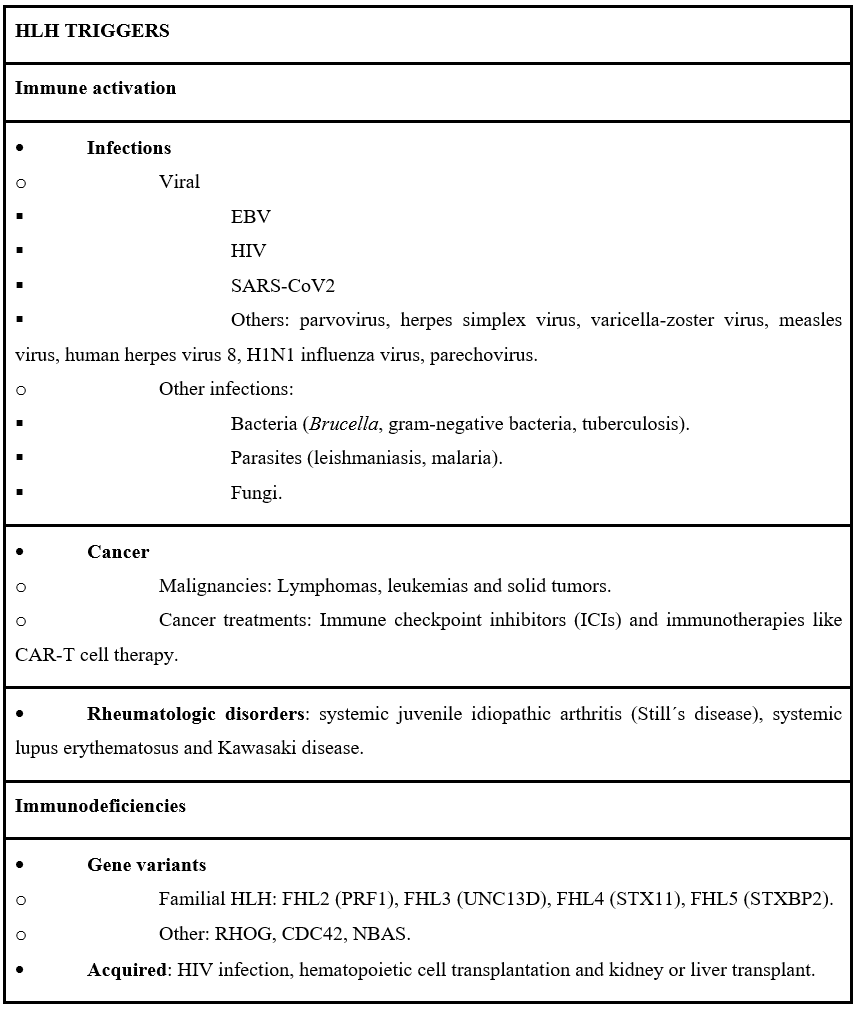

Table 3: HLH triggers.

EBV: Epstein Barr virus; HIV: Human immunodeficiency virus; SARS-CoV2: Severe acute respiratory syndrome coronavirus 2.

Triggers of HLH are crucial to identify because treating them may lessen the severity of HLH and, in some cases, enable avoidance of more cytotoxic HLH-specific therapy. The most important triggers include infections such as Epstein-Barr Virus (EBV) and hematologic malignancies like lymphomas. Autoimmune disorders and immunodeficiencies may also contribute to the underlying pathophysiology of the disease. The development of CMV-induced HLH in an immunocompetent adult, as in our case, is therefore unusual and clinically relevant. A full list of triggers can be found in the accompanying table (Table 3) [5].